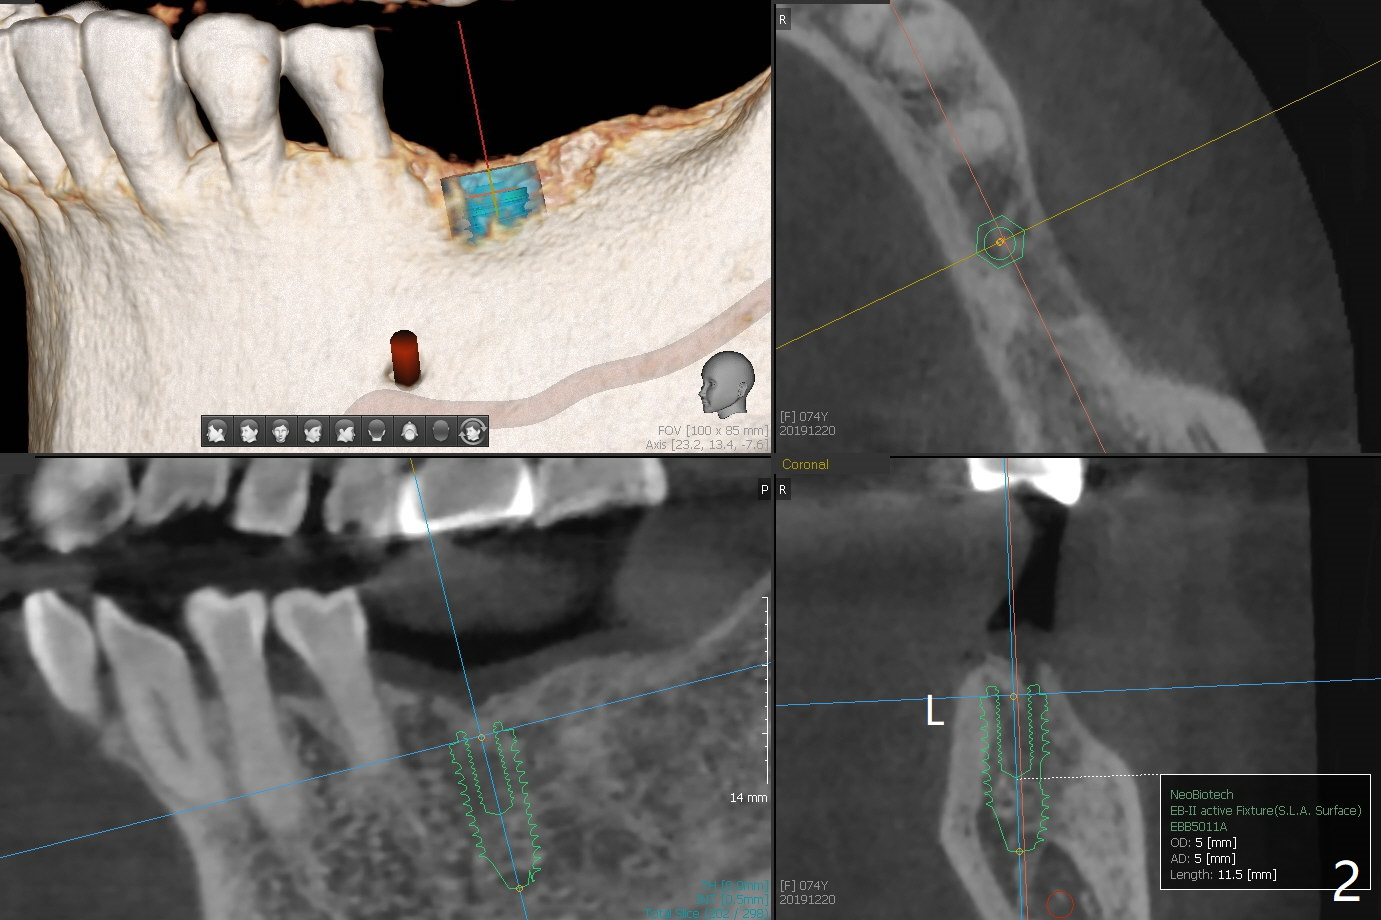

A 74-year-old woman returns for #19 implant consul-tation 5 years 7 months post cementa-tion at #3 (Fig.1). Since the implant at #3 (6x14 mm) has less ideal trajectory associated with free hand placement (Fig.3 (mild distolingual (L) thread exposure; Fig.1,4 (distal placemennt), guide will be fabricated for #19 implant placement. The lingual plate is thick and dense (Fig.2 L). To prevent drill and implant deviation buccally, a 5x11.5 mm implant will be placed as lingual as possible. A 5 mm cortical drill will be used before 2.2-4.5 mm ones being used for depth. The 4.0 mm drill will reach the final depth (apical underprep). A 17 mm long tissue-level implant will be placed. 17-5.5=11.5 mm (thread portion); 1.2 mm drill tip for the rough surface. Prepare 3.5x14 or 17 mm dummy implant to test the depth.